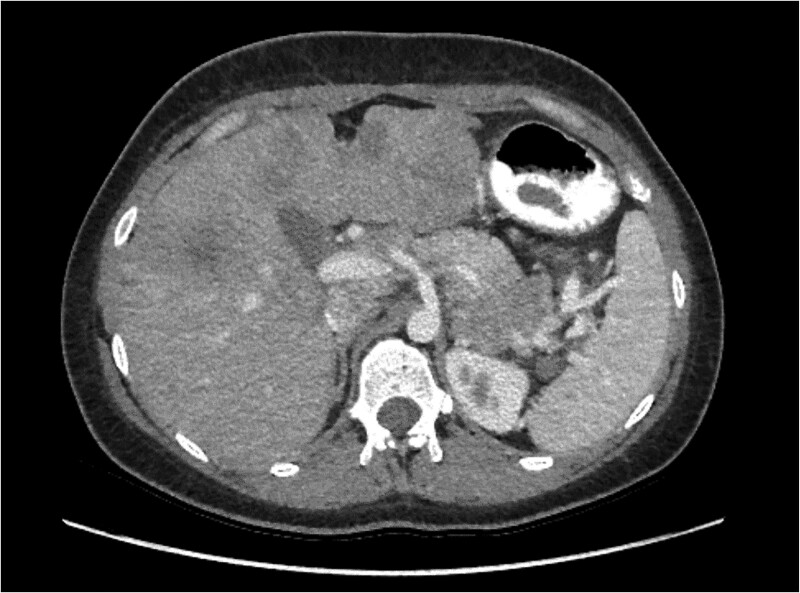

Insulinomas are rare neuroendocrine neoplasms and causes of hypoglycemia. They present with neuroglycopenic symptoms, including confusion and seizures. Suspected diagnosis must be confirmed through bloodwork and imaging. The majority of insulinomas are benign and cured surgically; less than 10% of insulinomas are malignant. Malignant insulinomas present a unique and rare challenge in managing persistent hypoglycemia and tumor burden. We present a case of a young woman who presented with Whipple triad and high-grade masses in her pancreas, liver, and distant lymph node metastases on imaging. Insulinoma was diagnosed. Hypoglycemia was managed with continuous dextrose infusion, diazoxide, and lanreotide. She was discharged on medical management and a continuous glucose monitor. Her metastatic disease is being treated with a capecitabine and temozolomide (CAPTEM) regimen showing 30% reduction in tumor burden. In conjunction with the National Institutes of Health, she is undergoing evaluation with numerous neuroendocrine tumor surgeons for cytoreductive surgery.